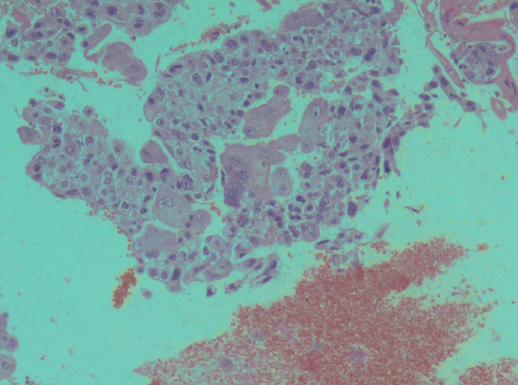

Figure 3: Section showing haemorrhagic and necrotic tumour composed of malignant-syncytiotrophoblast and cytotrophoblasts (x100).

figure 3